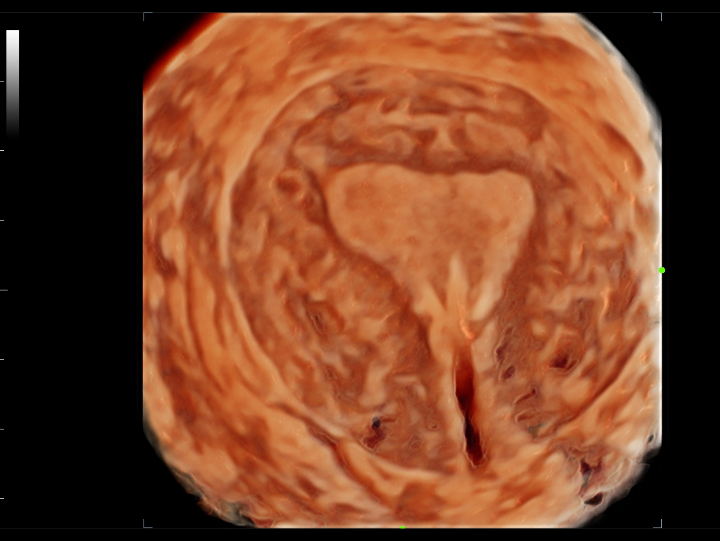

Pelvic ultrasound is considered as the first choice of imaging examination method to evaluate suspected gynecological diseases in women of all ages. Ultrasonography is usually the only necessary imaging examination to diagnose uterine, ovarian and adnexal diseases because of its wide availability, low cost and advantages of no ionizing radiation. With the development of volume ultrasound technology, 3D ultrasound has become a routine gynecological examination item. Through the acquisition of volume data, 3D ultrasound can display the uterus, cervix, ovary and uterine adnexa on any plane, and has more advantages in evaluating the uterine cavity.

UWN+ CEUS provides excellence contrast agent sensitivity and image penetration to get more diagnosis information for gynecology tumor or other difficult diseases. Also MindrayŌĆÖs STE (Sound Trouch Elastogtaphy) can quantitatively evaluate tissue stiffness which is helpful for previse diagnosis of difficult uterus, cervix and ovary diseases.